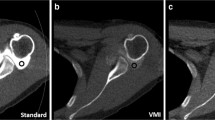

The results of interobserver variability for the relative visual grading score showed good agreement for an overall artifact (κ = 0.75), depiction of soft tissue (κ = 0.62), and cortical bone (κ = 0.61) between the two radiologists. In the pairwise comparison of the three MAR protocols, VMI + PB-MAR showed fewer overall artifacts than did the other two protocols, and when comparing VMI and PB-MAR, PB-MAR was found to have fewer overall artifacts (p < .001). Next, soft tissue was best depicted in the VMI + PB-MAR protocol, followed by PB-MAR in both the femoral and tibial regions (p < .001). For the depiction of cortical bone in the distal femur, PB-MAR showed the best performance, followed by VMI + PB-MAR (p < .001). However, in the tibial stem region, where metal artifacts are relatively small, all three MAR protocols depicted cortical bones to a similar extent (Fig. 3). Representative cases are shown in Figs. 4, 5, and 6.

Axial CT images of a 77-year-old female patient who underwent total knee arthroplasty surgery of the left knee joint reconstructed with the (a) non-MAR, (b) PB-MAR, (c) VMI, and (d) VMI + PB-MAR protocols. All images are shown in the bone window setting (window width = 2000 HU, window level = 500 HU). If the metal artifacts were not severe, all three MAR protocols reduced artifacts sufficiently, but the metal-bone interface was most apparent for the VMI + PB-MAR protocol. VMI, virtual monochromatic imaging; PB-MAR, projection-based metal artifact reduction

In this study, DECT-based protocols (VMI and VMI + PB-MAR) showed a reduced CNR compared to the projection-based protocol, and using the projection-completion method alone was most useful for the evaluation of bony structure in cases with severe artifacts. The reduction in the CNR can be explained by the higher photon energy used for VMI (120 keV) than the average energy of the polychromatic beam used in conventional CT (120 kVp), which is considered to be equivalent to 77 keV [25]. The problem of bone deletion has been reported as a pitfall of PB-MAR in several studies [26,27,28], and in a recent study by Laukamp et al [29], they concluded that PB-MAR is advantageous for the evaluation of soft tissue and that VMI was superior for the depiction of periprosthetic bone structure in patients with total hip replacement. However, in our study, when VMI + PB-MAR and PB-MAR were compared, the former was better in the evaluation of soft tissues, and PB-MAR alone was more useful in the evaluation of bone structure especially in cases with severe artifacts. Further studies are needed to confirm the clinical utility of this method in the diagnosis of postoperative complications in the bone and soft tissue, respectively.